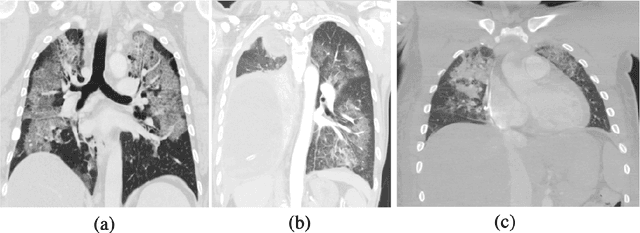

Abstract:Novel Coronavirus disease (COVID-19) is a highly contagious respiratory infection that has had devastating effects on the world. Recently, new COVID-19 variants are emerging making the situation more challenging and threatening. Evaluation and quantification of COVID-19 lung abnormalities based on chest Computed Tomography (CT) scans can help determining the disease stage, efficiently allocating limited healthcare resources, and making informed treatment decisions. During pandemic era, however, visual assessment and quantification of COVID-19 lung lesions by expert radiologists become expensive and prone to error, which raises an urgent quest to develop practical autonomous solutions. In this context, first, the paper introduces an open access COVID-19 CT segmentation dataset containing 433 CT images from 82 patients that have been annotated by an expert radiologist. Second, a Deep Neural Network (DNN)-based framework is proposed, referred to as the COVID-Rate, that autonomously segments lung abnormalities associated with COVID-19 from chest CT scans. Performance of the proposed COVID-Rate framework is evaluated through several experiments based on the introduced and external datasets. The results show a dice score of 0:802 and specificity and sensitivity of 0:997 and 0:832, respectively. Furthermore, the results indicate that the COVID-Rate model can efficiently segment COVID-19 lesions in both 2D CT images and whole lung volumes. Results on the external dataset illustrate generalization capabilities of the COVID-Rate model to CT images obtained from a different scanner.

Abstract:The novel Coronavirus disease, COVID-19, has rapidly and abruptly changed the world as we knew in 2020. It becomes the most unprecedent challenge to analytic epidemiology in general and signal processing theories in specific. Given its high contingency nature and adverse effects across the world, it is important to develop efficient processing/learning models to overcome this pandemic and be prepared for potential future ones. In this regard, medical imaging plays an important role for the management of COVID-19. Human-centered interpretation of medical images is, however, tedious and can be subjective. This has resulted in a surge of interest to develop Radiomics models for analysis and interpretation of medical images. Signal Processing (SP) and Deep Learning (DL) models can assist in development of robust Radiomics solutions for diagnosis/prognosis, severity assessment, treatment response, and monitoring of COVID-19 patients. In this article, we aim to present an overview of the current state, challenges, and opportunities of developing SP/DL-empowered models for diagnosis (screening/monitoring) and prognosis (outcome prediction and severity assessment) of COVID-19 infection. More specifically, the article starts by elaborating the latest development on the theoretical framework of analytic epidemiology and hypersignal processing for COVID-19. Afterwards, imaging modalities and Radiological characteristics of COVID-19 are discussed. SL/DL-based Radiomic models specific to the analysis of COVID-19 infection are then described covering the following four domains: Segmentation of COVID-19 lesions; Predictive models for outcome prediction; Severity assessment, and; Diagnosis/classification models. Finally, open problems and opportunities are presented in detail.